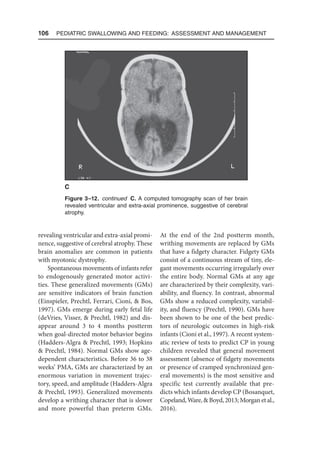

Ultrasound studies reveal nonnutritive

suckling/sucking and swallowing in most

fetuses by 15 weeks’ gestation (Moore et

al., 2015). Sucking, suckling, and sucking act

are terms often used interchangeably in the

literature to describe mouthing movements